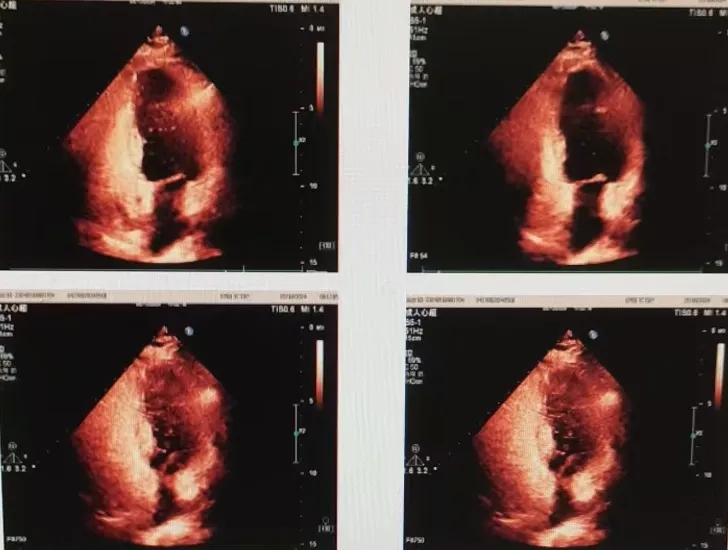

CDFI血流动力学:卵圆孔水平静息状态下0级,无右向左分流。Valsaval动作后可见中等量右向左分流。

右心声学造影:瓦氏动作后:Ⅱ级(左心腔内10-30个微泡/帧),中等量RLS。

超声所见:右心声学造影:两支10ml注射器,分别抽取1ml空气和8ml生理盐水,经三通管相连,回抽1ml静脉血,使三者在2支注射器间反复推注10次以上,充分混合后置于1支注射器内,将配置好的造影剂快速经右肘正中静脉推注后,右房右室即刻微泡显影,左房左室未见显影,嘱患者在压力检测表下用力呼气,压力达40mmHg以上,左房、左室内可见30个以内微泡显影。

超声结论:右心声学造影:阳性(静息状态下0级,无右向左分流;瓦氏动作后Ⅱ级,中等量右向左分流)。